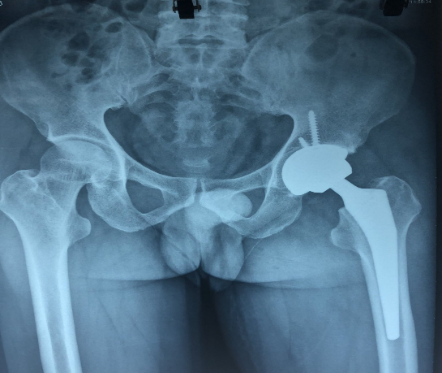

Ngược lại với trường hợp trên thì trường hợp thứ 2 là bệnh T.V. T sinh năm 1970 vào viện với lý do đau khớp háng trái nhiều năm, đến mức phải đi tập tễnh, bệnh nhân đã đi khám nhiều nơi nhưng không tuân thủ điều trị. Kết quả chụp Xquang cho thấy tổn thương là các ổ khuyết xương dưới sụn, bờ của chỏm xương đùi biến dạng được xếp loại giai đoạn III theo Arlet – Ficat và có chỉ định phải phẫu thuật thay chỏm xương đùi. Ê kíp của BSCKII. Hoàng Tuấn Minh, Ths.Bs. Lê Đức Anh, BsCKI. Trần Thành Trung khoa Chấn thương chỉnh hình, với nhiều năm kinh nghiệm đã thay thành công khớp háng cho bệnh nhân. Sau phẫu thuật 1 tháng bệnh nhân hết đau và đã đi lại được bình thường.

Hình ảnh Xquang của bệnh nhân trước và sau phẫu thuật thay khớp háng